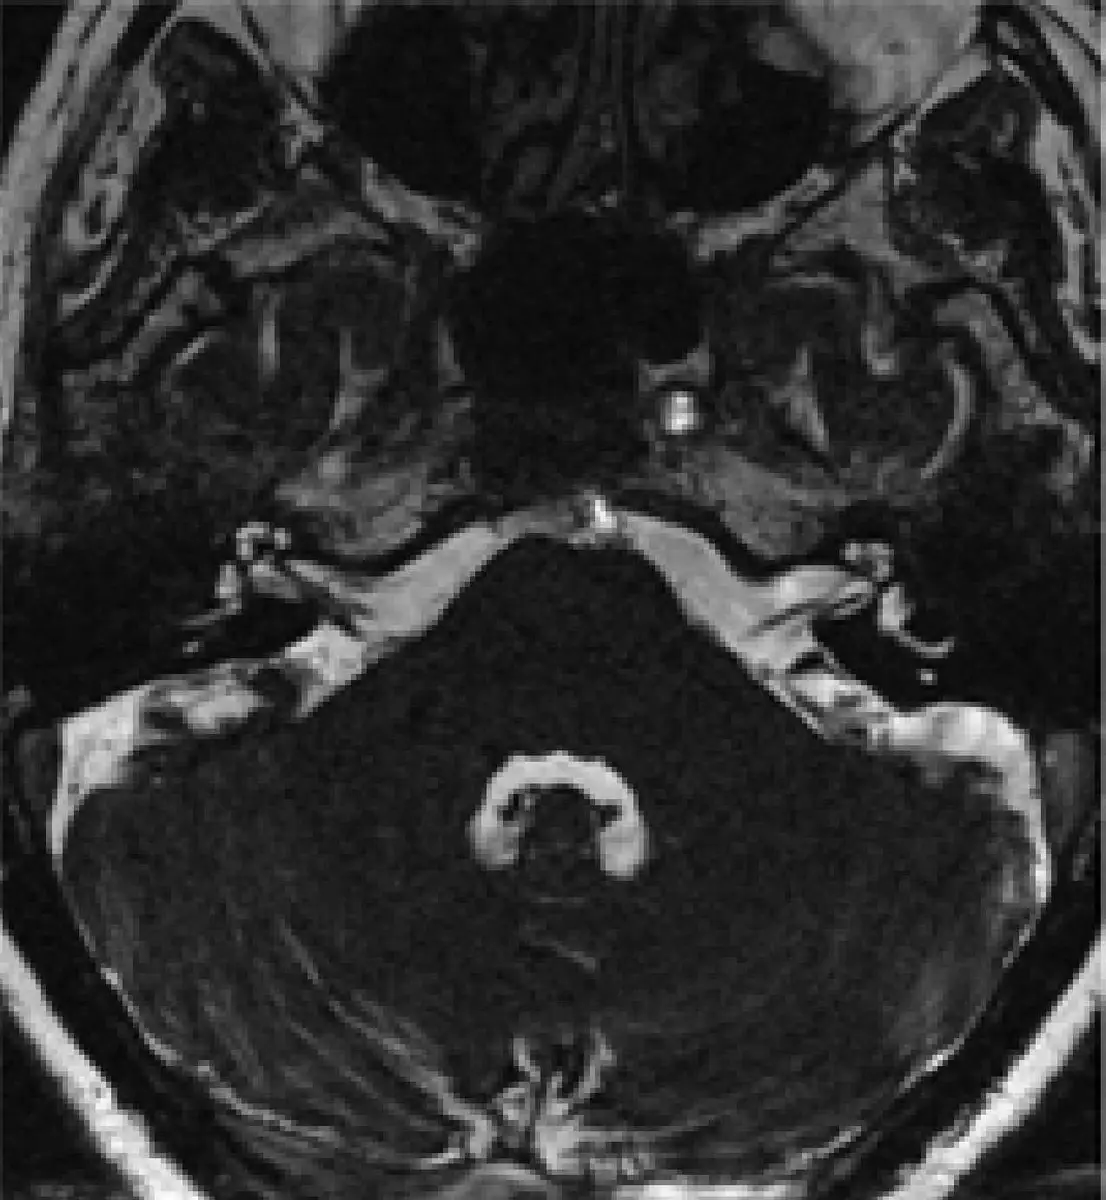

附圖最可能 為下列中何種脈衝序列所產⽣的 MR 影像?

本題考察 MRI 脈衝序列(pulse sequence)的影像特徵辨識,重點在於辨別 CISS(Constructive Interference in Steady State)序列的典型影像外觀。CISS 是穩態自由進動(steady-state free precession, SSFP)家族的 3D 梯度回波序列,以 T2/T1 訊號對比為基礎,產生腦脊髓液(cerebrospinal fluid, CSF)高亮度、神經組織對比極佳的影像,廣泛用於後顱窩(posterior fossa)及腦神經(cranial nerve)的高解析度成像。

附圖為後顱窩層面的軸位(axial)MRI 影像,顯示小腦(cerebellum)及相鄰結構。影像特徵如下:

- CSF 呈極高訊號(亮白色):腦脊髓液在整張影像中呈現明亮的白色訊號,與周圍神經組織形成鮮明對比。這是 T2/T1 訊號加權的 SSFP 序列特徵——CSF 的 T2/T1 比值高,導致其訊號遠高於腦實質。

- 空間解析度極高:小腦葉(cerebellar folia)的細微結構及腦溝(sulci)均清晰可辨,達次毫米級(submillimeter)解析度,這是 3D CISS 序列的標誌性優勢。

- 無擴散限制模式:影像並非 DWI 的擴散加權對比